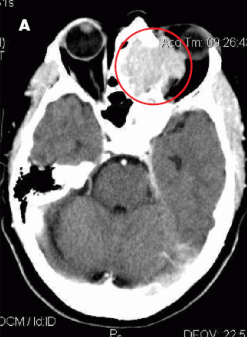

The patient had moderate proptosis; extraocular motions of the left eye were restricted in all directions. She had no lymphadenopathy. Oropharynx was visually unremarkable; however, fiberoptic nasopharyngoscopy revealed a posterior superior nasal cavity mass. A contrast CT scan of the head showed a large mass lesion at the level of the ethmoid sinus, eroding into the left orbit and displacing the left globe (A).

MRI of the head showed a 5.3 x 4.2 x 4.2-cm enhancing mass at the base of the brain that extended into the nasal cavity, with erosion into the cribriform plate, ethmoid sinuses, and planum sphenoidale. Results of an ethmoid sinus mass biopsy confirmed high-grade diffuse large B-cell lymphoma. Staging CT scans showed no metastatic disease, and cerebrospinal fluid analysis revealed no malignant cells. A bone marrow biopsy specimen showed no evidence of light chain monoclonality, no overt evidence of B-cell lymphoproliferative disorder on flow cytometry analysis, and no lymphoma. This was consistent with stage IAE disease.